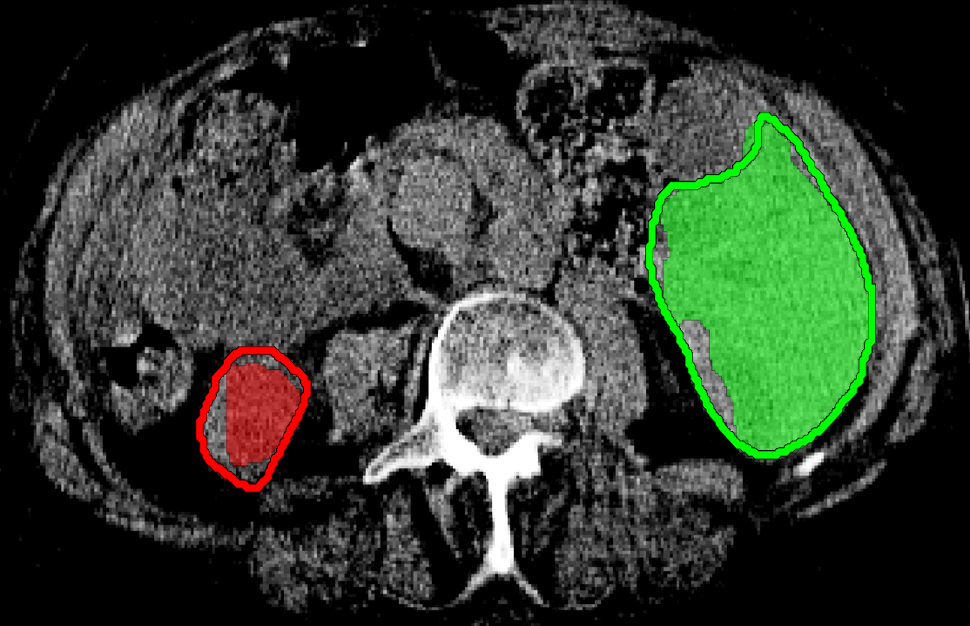

In the following set of experiments we show the benefit of incorporating our Hedgehogs term (6) to the well studied Potts model segmentation energy, i.e. data term + smoothness term, for multi-object segmentation in 2D and 3D. We will also give an illustrative real life example to show that the hedgehog shape is more general than star-shape [25]. The results shown in this section for our method were generated using when computing the hedgehog shape constraints, also we did not enforce any shape constraints on the background model. Also, the same smoothness weight is used when comparing methods unless stated otherwise.

For the example shown in Fig.9(a), (b-c) show Potts model results for and 6, respectively. It should be noted that is the smallest smoothness weight that did not result in over-segmentation when using Potts. However, the result in Fig.9(c) is biased towards smaller objects (notice star tips) because by increasing the smoothness weight we are also increasing the shrinking bias. Over-segmented results as the one in Fig.9(b) could be avoided without increasing the shrinking bias, simply by incorporating multi-shape priors. Our method which incorporates Hedgehogs shape priors with Potts model was able to find a better segmentation, see Fig.9(d).

The objective of the example shown in Fig.10(a) is to segment left and right lungs, and the background. Potts model result shown in Fig.10(b) has holes, i.e. part of the background appears in the middle of the lungs. Furthermore, Potts model converged to biased color models where the right lung preferred brighter colors while the left preferred darker colors. Similar to the previous example, increasing for Potts model will increase the shrinking bias and it becomes hard to segment the elongated part of the the right lung. Using multi-star which is a generalization of [25] to multi-object segmentation is not enough because the right lung is not a star-shape. To be specific, there is no point inside the right lung that could act as a center of a star-shape that would include it. Fig.10(d) shows the result for our method, where user scribbles were used to enforce shape constraints compared to using a single pixel per label [9].